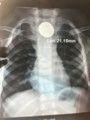

▲胸片

错误的判断导致病情持续恶化,直到8月14日,看着依然只能吃流食、病情不断加重的儿子,浩浩妈带着他去新都当地一家医院做检查——胸片显示,一个直径2.2厘米的圆形异物卡在了浩浩食管的中上部?!爸猩喜康拇笱鼙冉戏岣唬O招愿?,医生说病情很紧急,告诉我小医院做不了,建议到市级医院看看。”